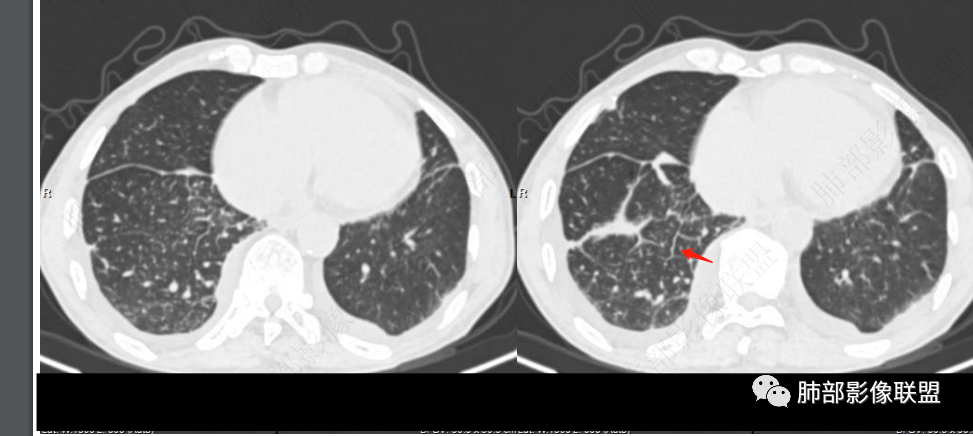

双肺叶透亮度呈磨砂状,并弥漫性以肺腺泡为单位GGO结节,边缘模糊,肺动脉高压表现,双肺下叶肺动脉分支明显增粗>邻近支气管径,小叶间隔增厚,叶间积液和少量胸腔积液,方向1.PVOD病并肺泡出血,2.心衰表现!

老年男性,胸闷、浮肿10天,左肺尖可见肺大泡影,两肺散在纤维索条影,右肺见弥漫性腺泡结节,以右肺上叶为著,右肺下叶局部小叶间隔增厚,双侧胸腔、右侧叶间裂及心包积液,结合实验室及影像检查,符合心衰及肺水肿表现,右肺部病变符合PVOD表现。

两边血管不对称,栓塞先考虑

左肺明显肺野透亮度增加,右肺明显肺水肿!右肺血管束稀疏,D二聚体明显高!首选左肺肺栓塞可能

双肺透过度不均匀,右肺减低,可见腺泡结节影,中央间质、周围间质增厚,少量积液。肾衰病史首先考虑肾性肺水肿。

老年女性,胸闷,水肿,气短,bnp高,临床有心功能不全,心彩无左衰依据,胸部ct右肺磨玻璃,小结节,小叶间隔增厚,血管不对称,考虑pe

2.右肺广泛密度增高、腺泡结节样磨玻璃影,血管影明显扩张,小叶间隔增厚。

4.左肺相对广泛低密度、血管纤细(显著)。